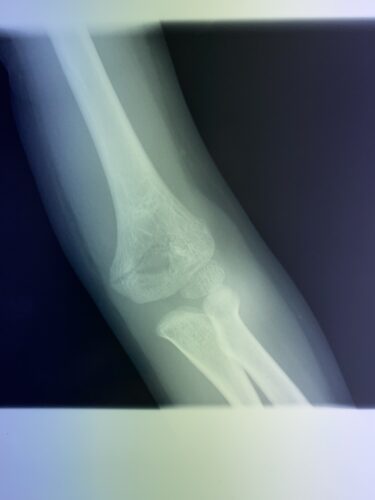

第28回整骨研究会「賜恩」研修会開催

春日部市市民活動センター(上腕骨顆上骨折)